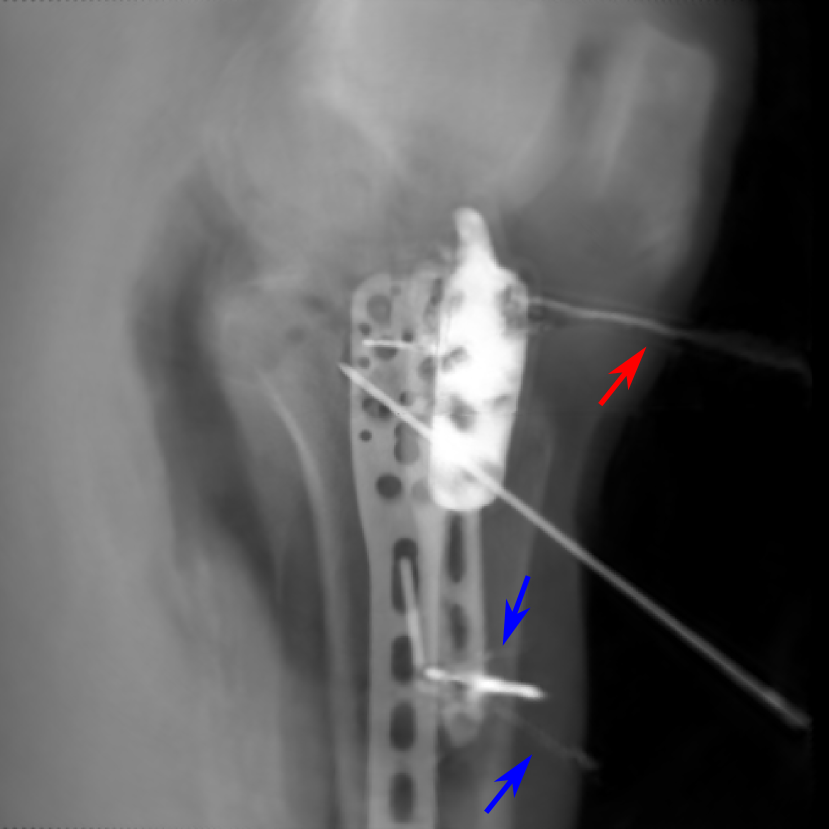

(a) 0superscript00^{\circ} perspective

(b) 0superscript00^{\circ} and 180180180 RGB

(c) Pix2pixGAN

Figure 18: An example from the real cadaver data, where the Pix2pixGAN predicted metal rod is distorted (indicated by the red arrow) and certain K-wire shadows from perspective projection images remain (indicated by the blue arrows).

In the real cadaver data, certain metal implants are distorted in Pix2pixGAN predictions. For example, the long metal rod indicated by the red arrow is no longer straight in Fig. 18(c), although its position is between the corresponding magenta and green rods in Fig. 18(b). Another limitation is that certain structures like thin K-wires from 0superscript00^{\circ} and 180superscript180180^{\circ} perspective projection images will remain as shadows in the Pix2pixGAN prediction, for example, those indicated by the blue arrows in Fig. 18(c).

In practice, the perspective deformation corrected image can be compared with the input perspective images to check whether false positive and false negative structures occur.